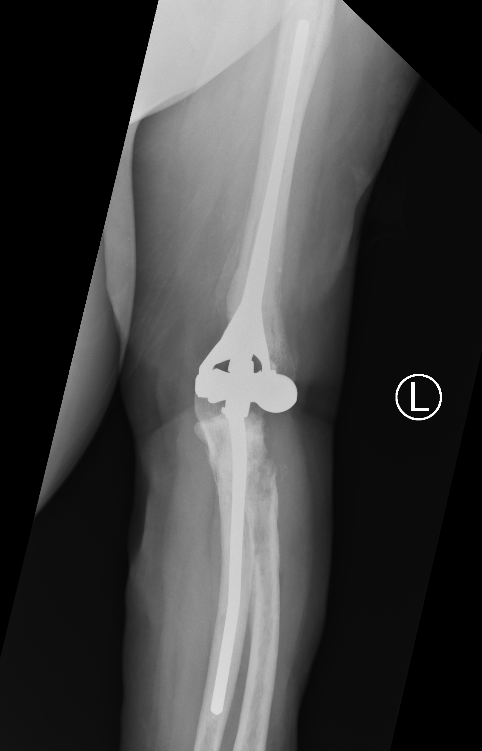

Coonrad-Morrey Discovery Elbow Latitude

Arthroplasty

4. Trial reduction

5. Insert cement restrictors / implant ulna and humeral prosthesis

6. Insert bone graft under anterior flange

7. Link components

8. Repair collaterals if needed